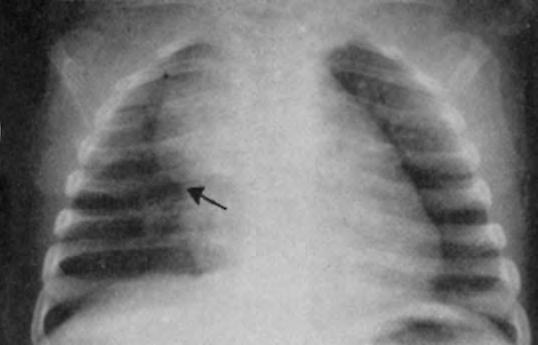

Sistema linfático

El timo es de gran tamaño, aunque puede disminuir gradualmente pasados los dos primeros días de vida (Fig. 2.1.6). Los ganglios linfáticos no suelen ser palpables e incluso en condiciones patológicas tardan en producirse adenopatías, todo ello en relación con las condiciones de inmadurez inmunitaria.